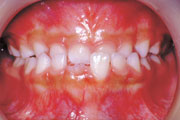

症例4:上顎前突